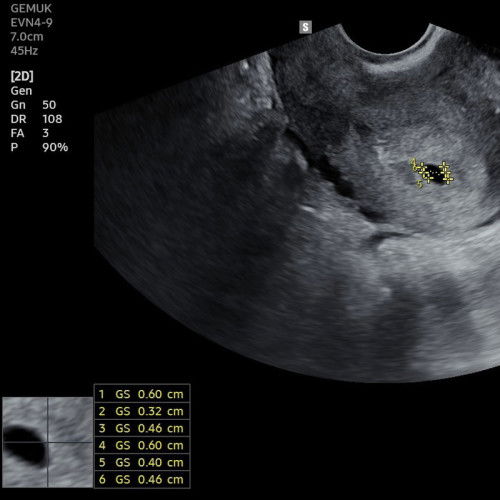

Baru terlihat kantungnya saja

Kalau dari hitungan HPHT sdh 6 minggu 5 hari, tp pas di usg kemungkinan masih 4-5 mingguan karna masih kelihatan kantungnya saja. Adakah yg sama seperti ini bunda? Doakan semoga next USG sdh terlihat janinnya ya bunda🥹 #sharing #masyaaAllahTabarakallah